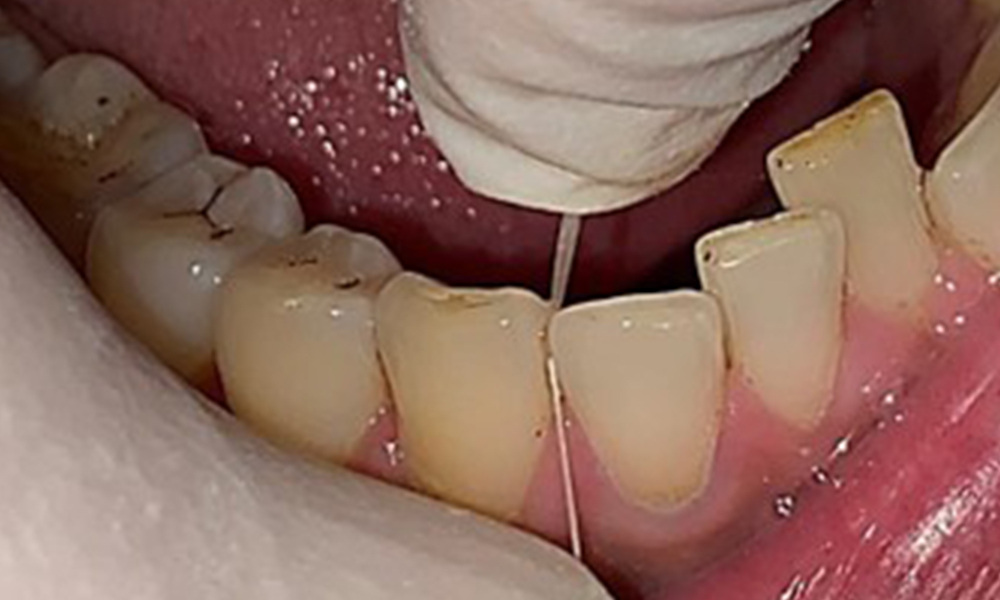

Zugleich ist es notwendig die Interdentalraumbürstchen, welche der

Patient täglich verwendet nach der richtigen Größe zu überprüfen und den Patienten zu bestärken diese konsequent zu benutzen (Abb. 9). Eine

gute Mundhygiene ist unabdingbar, um das Parodontitisrisiko durch das Rauchen zu minimieren.